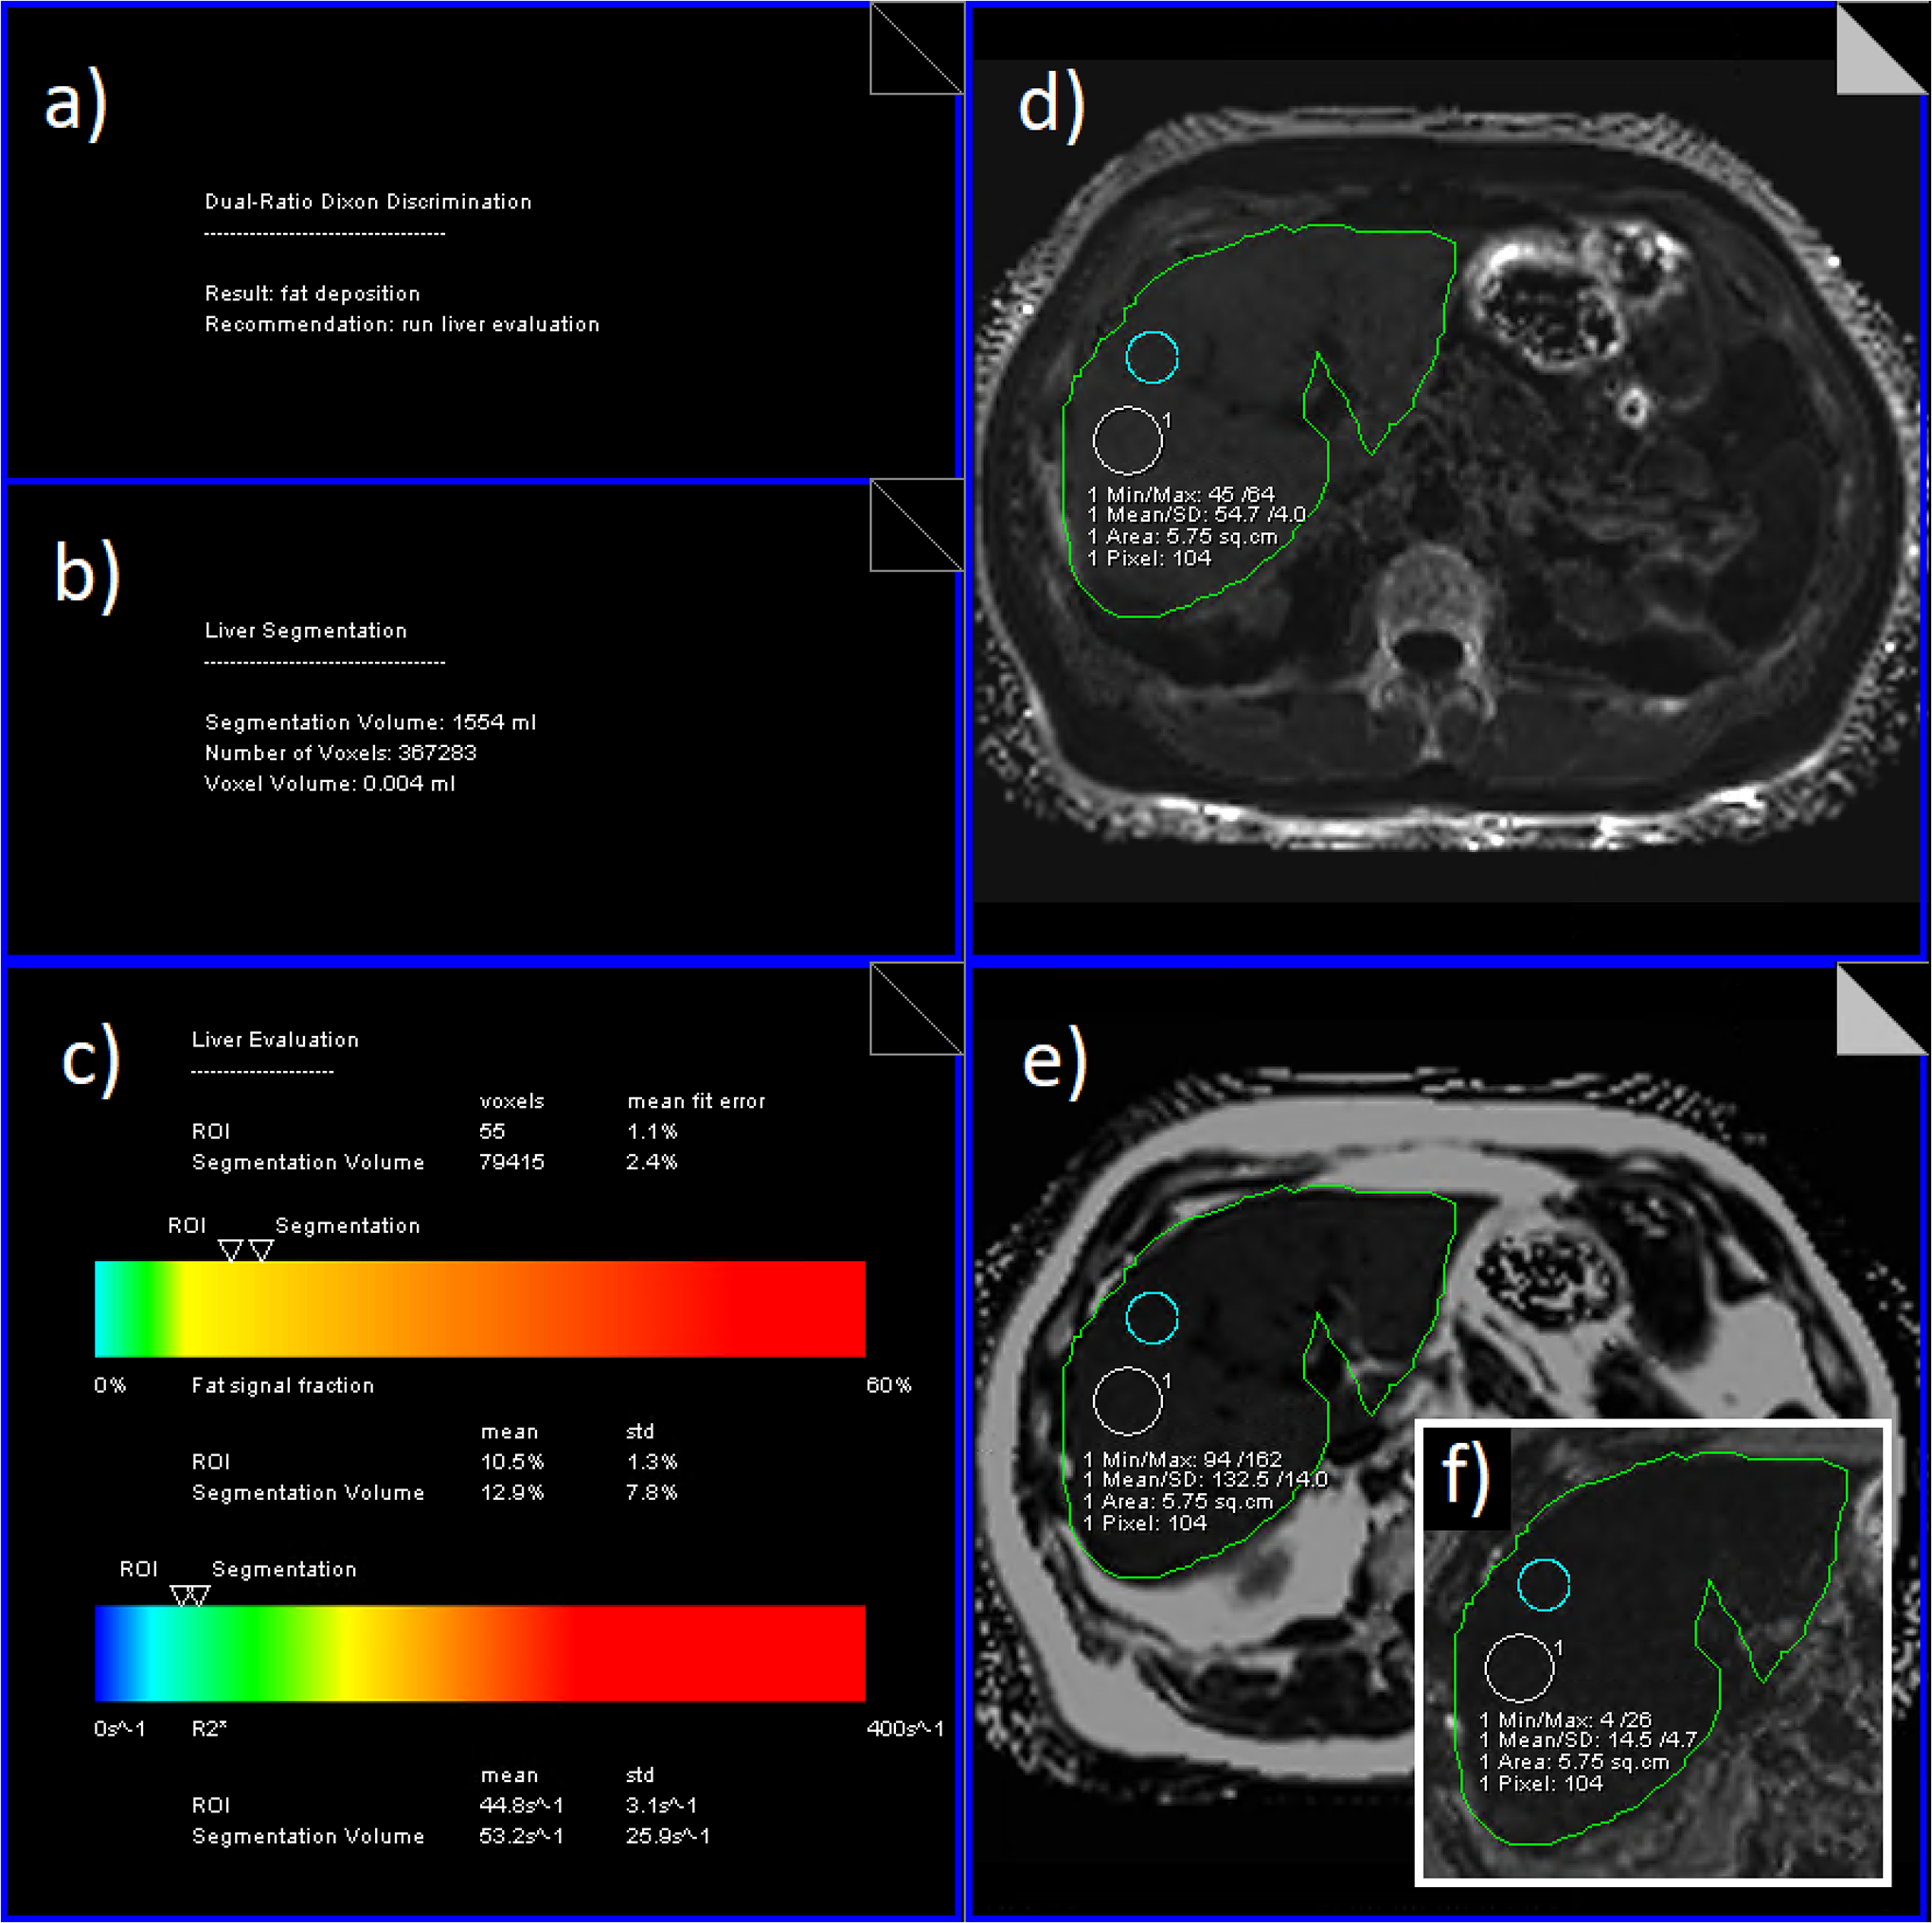

Some inline reporting is integrated: a typical clinical measurement program always contains a high-resolution T1-weighted two-echo VIBE Dixon protocol as anatomical overview and/or pre-contrast-injection scan. For this, an inline liver segmentation and dual-ratio discrimination analysis can be activated.58 The former yields a liver volume; the latter an early assessment whether iron overload, fatty infiltration, or a combination might be present. The liver segmentation result, together with an ROI which can be pre-planned at scan time is propagated to the processing of any subsequent multi-echo acquisition, where it is used for automated calculation and reporting of mean values, as shown in Figure 7. The maps can still be used for manual ROI analysis.

Figure 7.

Inline results from LiverLab product (Siemens Healthineers) at 3T of a 55-yr old male. From preceding two-echo Dixon a) Dual-ratio discrimination result (fat deposition), b) segmentation volume (1554 ml); from multi-echo Dixon c) report with extracted values of R2* (inline ROI 45s−1 ~ LIC 0.6 mg/g using Hernando29), PDFF (inline ROI 10.5%), and GoodnessOfFit (inline ROI 1.1% = very good) d) R2* map with projected liver segmentation, inline ROI and manual ROI (55s−1, also showing the heterogeneity of the R2* distribution), e) corresponding PDFF map (manual ROI grayscale value 133 ~ 13.3%), f) cut-out of GoodnessOfFit map (manual ROI grayscale value 15 ~ 1.5% = very good).

To assess the reliability of the estimated R2/R2* maps, quality assurance metrics can be used. One vendor (LiverLab, Siemens Healthineers) provides a goodness-of-fit map for quality control, shown in Figure 7.78 Confidence maps, e.g., based on signal model consistency and SNR can provide automated quality assurance of the estimated R2/R2* values and enable reliable ROI selection, which can improve the accuracy and reproducibility of MRI-based LIC estimation. A recent study has developed a fully automated algorithm to generate confidence maps and identify reliable regions for mean liver R2* estimation by accounting for the quality of acquired signal, B0 field map estimation, and local susceptibility effects.75 These confidence maps can increase the reliability of MRI-based LIC estimation.